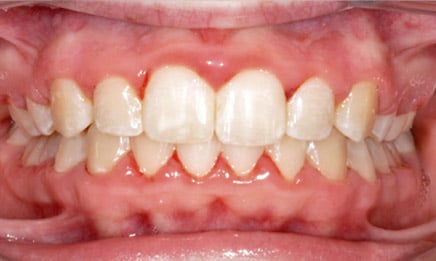

The main benefits from this treatment include improving function and appearance of the teeth and smile, moving permanent teeth into their proper positions, aligning the jaw, and preventing future problems due to poor alignment.

As you can see, there are so many different reasons for braces. Getting treated as a youth is not only much easier for the patient (socially), but the outcome will be much better as we are able to start aligning things as the body is growing.